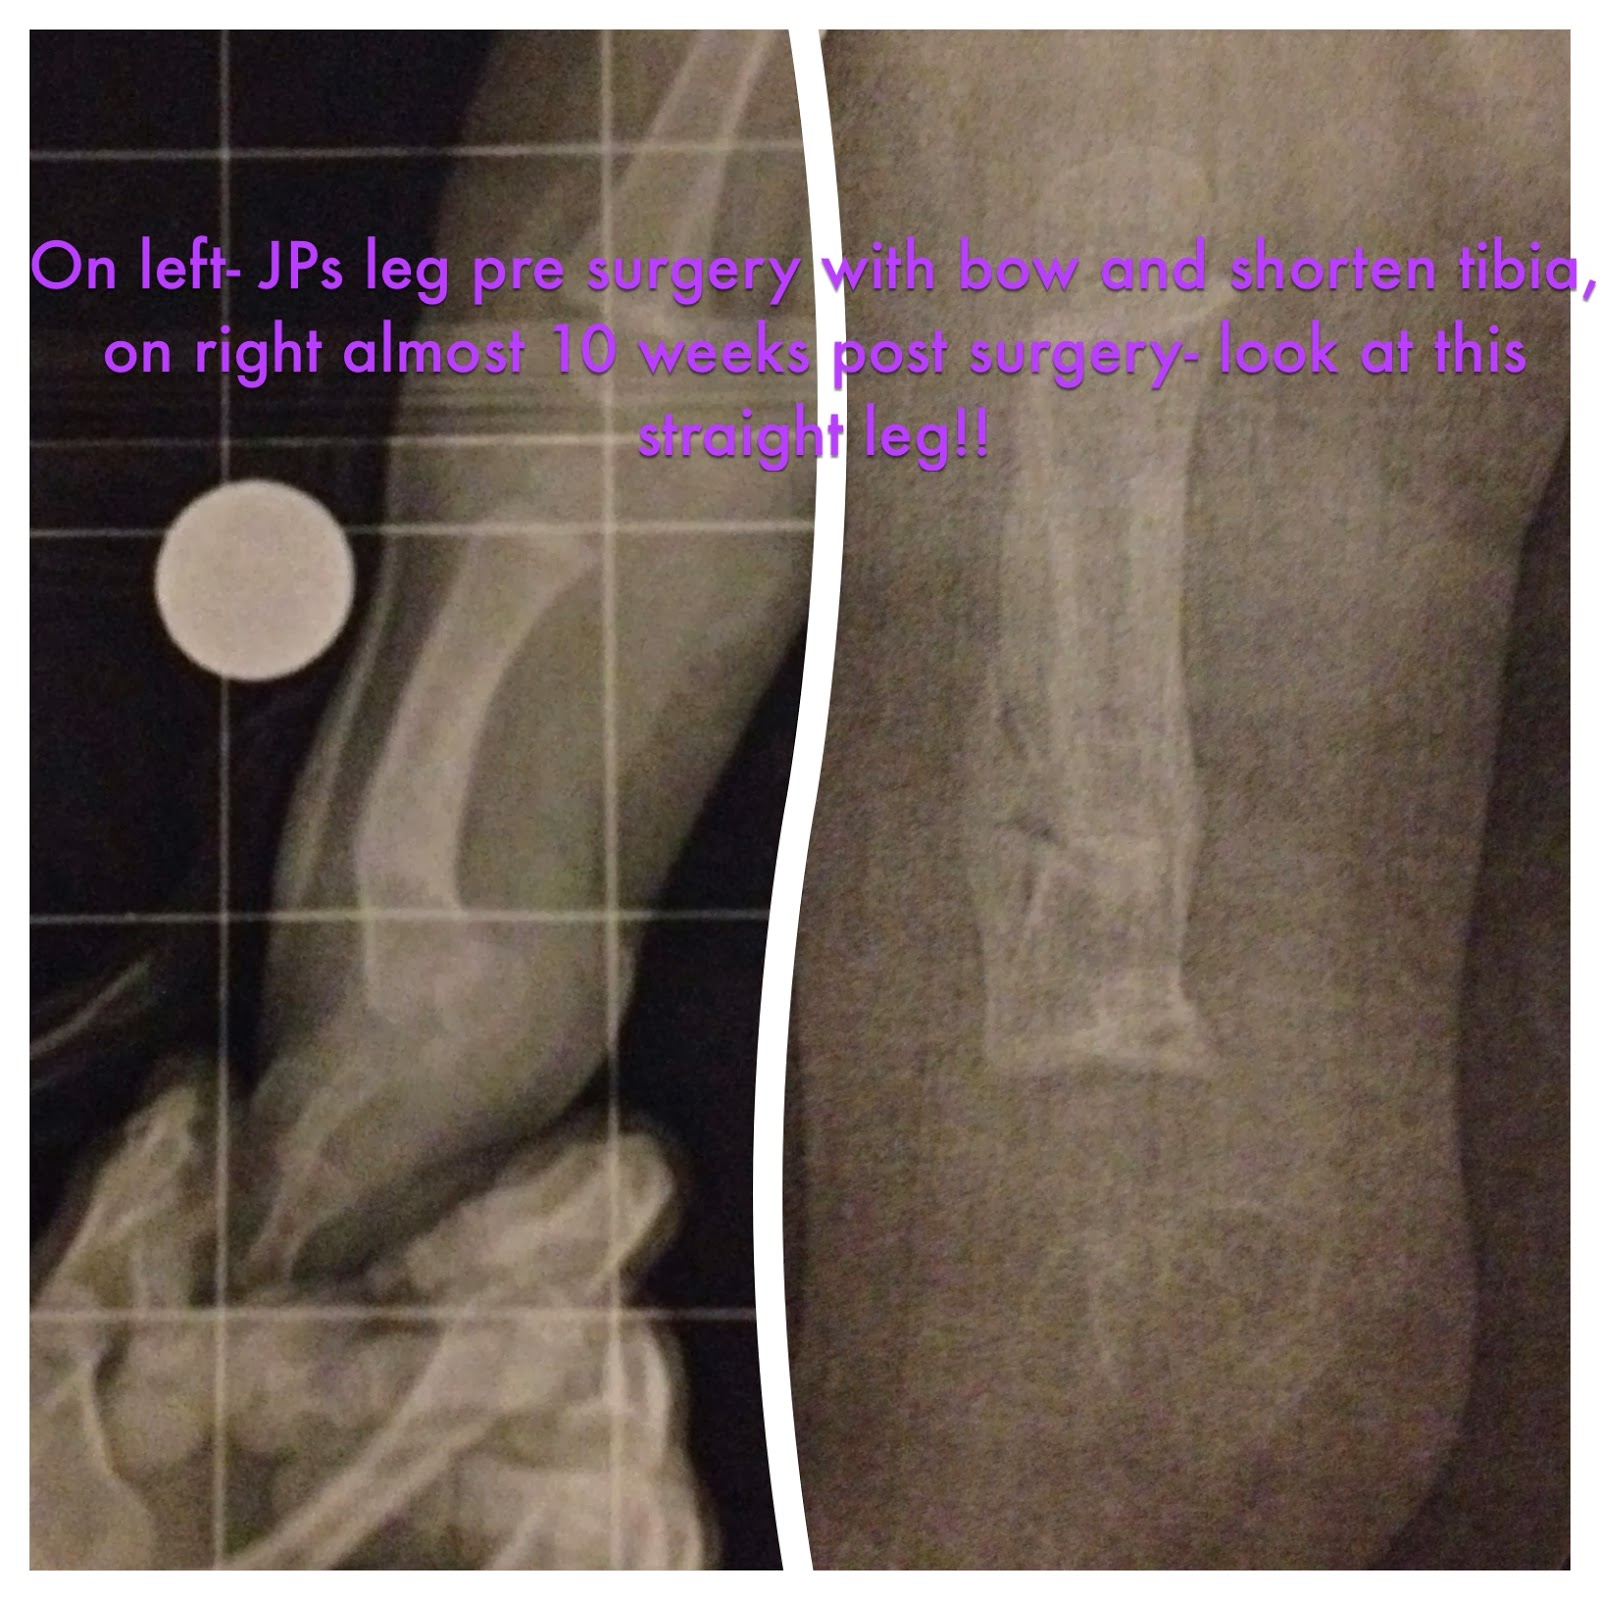

Here we are two years later- our baby is completed on track developmentally. And has come through surgery beautifully! He has taught us so much and we see so many changes in him! Below are the changes his leg has taken on.

And now, we have 4 months off- from cast changes, doctor visits etc! Just us getting our baby boy up and moving again...and he's already showing signs he's ready! We have come such a long way in two years! Sadly we'll have to start thinking about JP's next surgery soon, but for now it's Physical Therapy and getting him walking again!